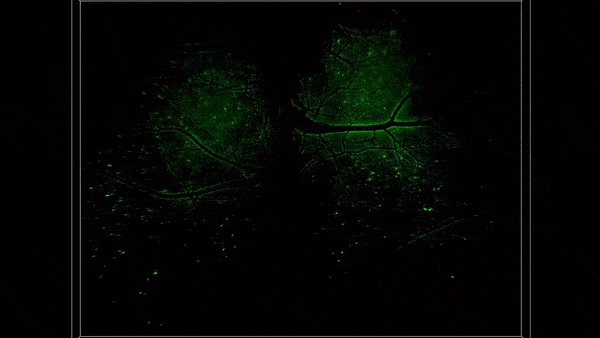

研究团队介绍,在兼具厘米级三维视场与亚细胞分辨率的同时,该仪器能以20Hz的高速三维成像速度实现长达数十小时的连续低光毒性观测。相比当前市场上最先进的商业化荧光显微镜,该仪器在同样分辨率下的成像视场面积提升近百倍,三维成像速度提升数十倍,有效观测时长提升上百倍。这一前所未有的跨空间和时间的多尺度成像能力,为复杂生物过程研究提供了全新视角。区别于传统光学显微镜聚焦于单个细胞内的物质交互过程,该仪器使得研究人员可以首次以全景方式动态观测哺乳动物器官尺度细胞精度的组织异质性,在活体组织中原位研究大规模多样化细胞在完整生理与病理过程中的动态交互行为。

目前,研究团队利用RUSH3D系统在脑科学、免疫学、医学与药学等多学科产出一系列成果。例如,首次在活体小鼠上以单细胞分辨率实现了覆盖大脑皮层2/3层的高速长时程三维观测,捕捉了多感官刺激下皮层各脑区的各异性响应模式,能够连续多天以单神经元精度追踪大规模神经响应;首次观测到急性脑损伤后多脑区的免疫反应,发现大量中性粒细胞从非血管区域往脑内的迁移与回流过程;首次在小鼠免疫反应过程中同时观测到了淋巴结内多个生发中心的形成过程,以及T细胞在不同生发中心之间的迁移现象。